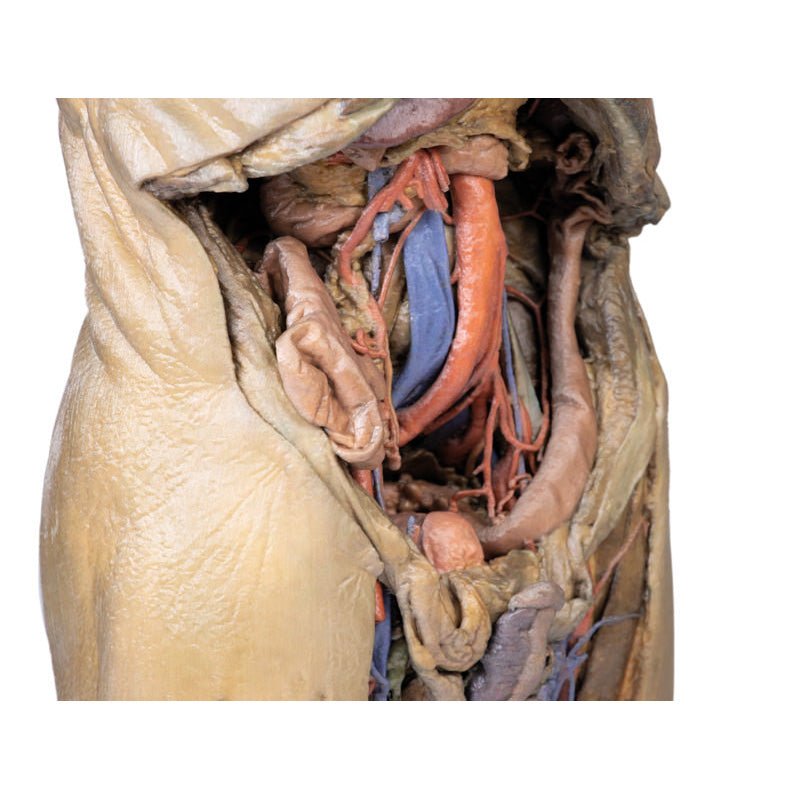

The epigastric and hypochondriac regions

Within the abdomen, the anterior abdominal wall, greater omentum, and

much of the gastrointestinal tract has been removed alongside the parietal peritoneum over the posterior

abdominal wall to expose retroperitoneal organs and structures. In the superior abdomen, the terminal portion of

the oesophagus has been retained and can be seen entering the cavity just lateral to the left lobe of the liver.

The removal of the stomach has exposed the extent of the pancreas from the head (positioned within the arc of

the duodenum) to the tail extending to the capsule of the spleen preserved in the left hypochondrium. Superior

to the pancreas, the splenic artery and common hepatic arteries can just be observed spanning across the narrow

space between the pancreas, diaphragm and liver. The splenic follows its archetypical ‘tortuous route’

towards the spleen, and strongly divides prior to reaching the hilum (and adjacent to the splenic vein). The

common hepatic can be seen dividing into the gastroduodenal (visible again as a cut vessel just inferior to the

duodenum) and giving off the right gastric artery; these vessels lie superficial relative to the hepatic portal

vein. The superior mesenteric artery and vein can be seen passing anteriorly near the head of the pancreas and

horizontal part of the duodenum, and the retained ileocolic artery can be traced to the caecum of the large

intestine in the lower right quadrant of the abdomen. The inferior mesenteric vein can be, in part, appreciated

arising from the retained superior rectal vein ascending from the undissected true pelvis and spanning across

the superficial aspect of the descending thoracic aorta.

Inferior to the liver the gallbladder can be viewed just between the right and left anatomical lobes. On the left, the passage of the renal artery and vein can be seen just deep to the pancreas, and the ureters can be observed descending from the partially exposed kidney across the superficial surface of the exposed psoas major and minor muscles.

The umbilical and lumbar regions

Most of the organs occupying the umbilical and lumbar regions of the abdomen

have been removed in order to expose structures in the posterior abdominal wall. In the midline, the descending

abdominal aorta and inferior vena cava dominate the region, with the testicular arteries and veins isolated and

traceable towards the inguinal regions. Two right lumbar arteries are visible arising from the aorta, and

despite removal of the mesenteries and most of the colon the inferior mesenteric artery can be seen giving rise

to the left colic, sigmoid and superior rectal arteries. On the right side of the specimen inferior to the

kidney, the subcostal, iliohypogastric and ilioingual nerves are exposed alongside the circumflex iliac artery.